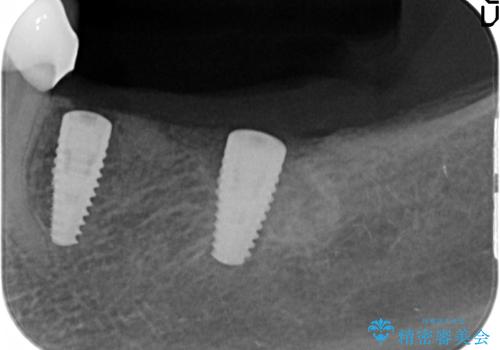

咬合機能を回復し、満足して食事を行えるようインプラント治療を計画します。

- 80万円(インプラント×2・アバットメント×2・ジルコニアクラウン×3)費用は治療当時の料金となります